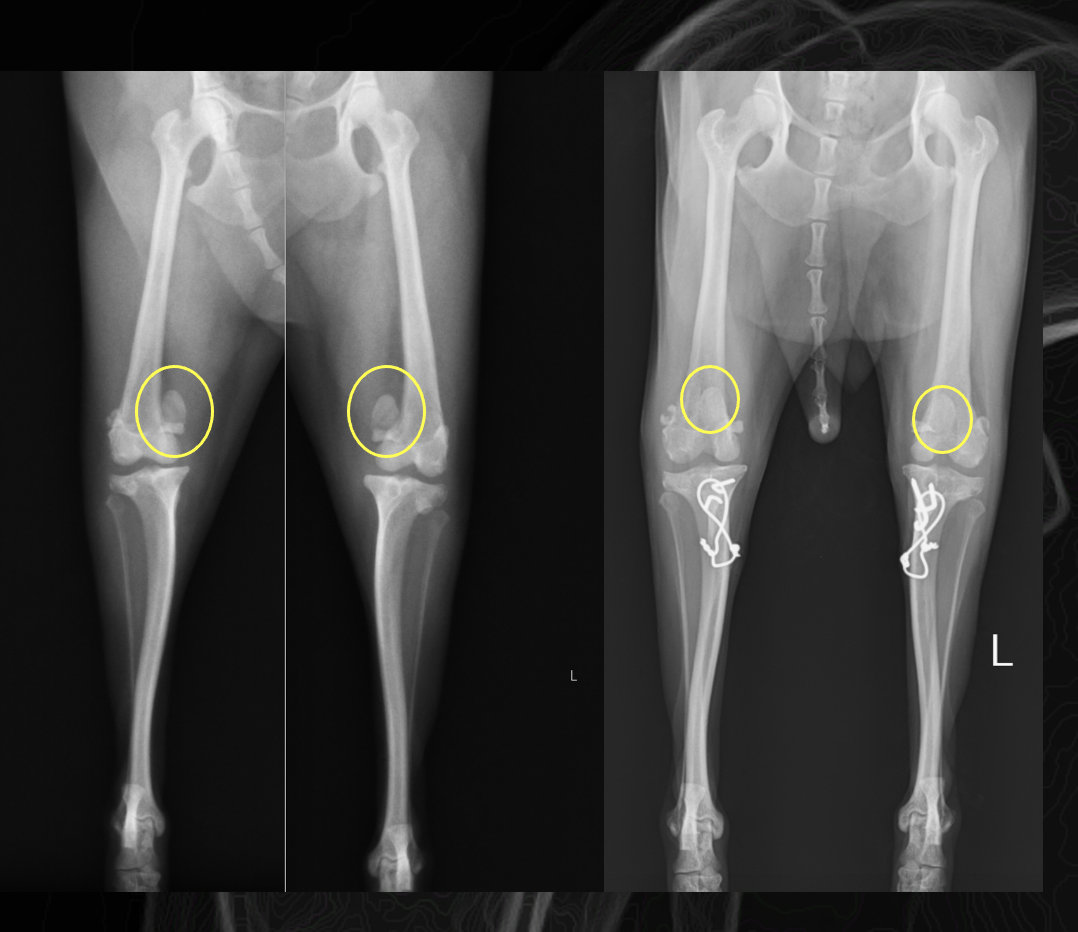

術後のレントゲン画像です。もともと内側にあった膝蓋骨が大腿骨の正しい位置(中央)に整復されているのがわかります。

脛骨粗面転移術です。下の脛骨と呼ばれる骨の、粗面という部分を一部切断し、外側にずらし、ピンで固定しています。このピンは抜かなくて大丈夫です。

両側脱臼の場合片側ずつやる場合もありますが、基本的には両側同時に手術する場合が多いです。両側同時の方が、術後の足のつき方が良いケースが多く(両側だと着かざるを得ないため、回復が早くなります)、麻酔も1回で終了するためです。最近では年間で40から50件ほどのパテラのオペがあり、関節疾患の中では多い疾患となっています。